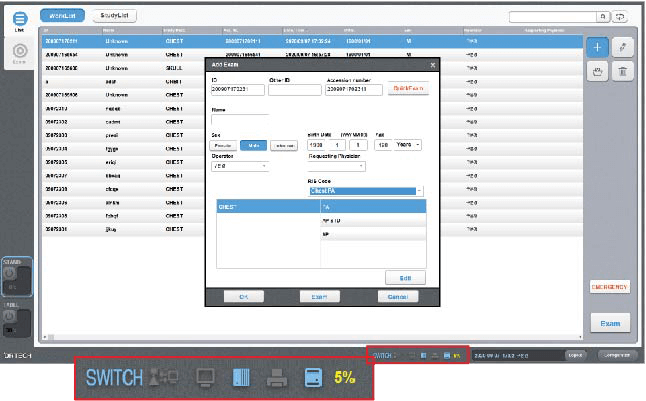

UI/UX Conveniente para mejorar su flujo de trabajo

- Proceso de registro de pacientes fácil y sencillo.

- Comprobación del estado de la conexión en tiempo real.

- Soporta 18 idiomas.